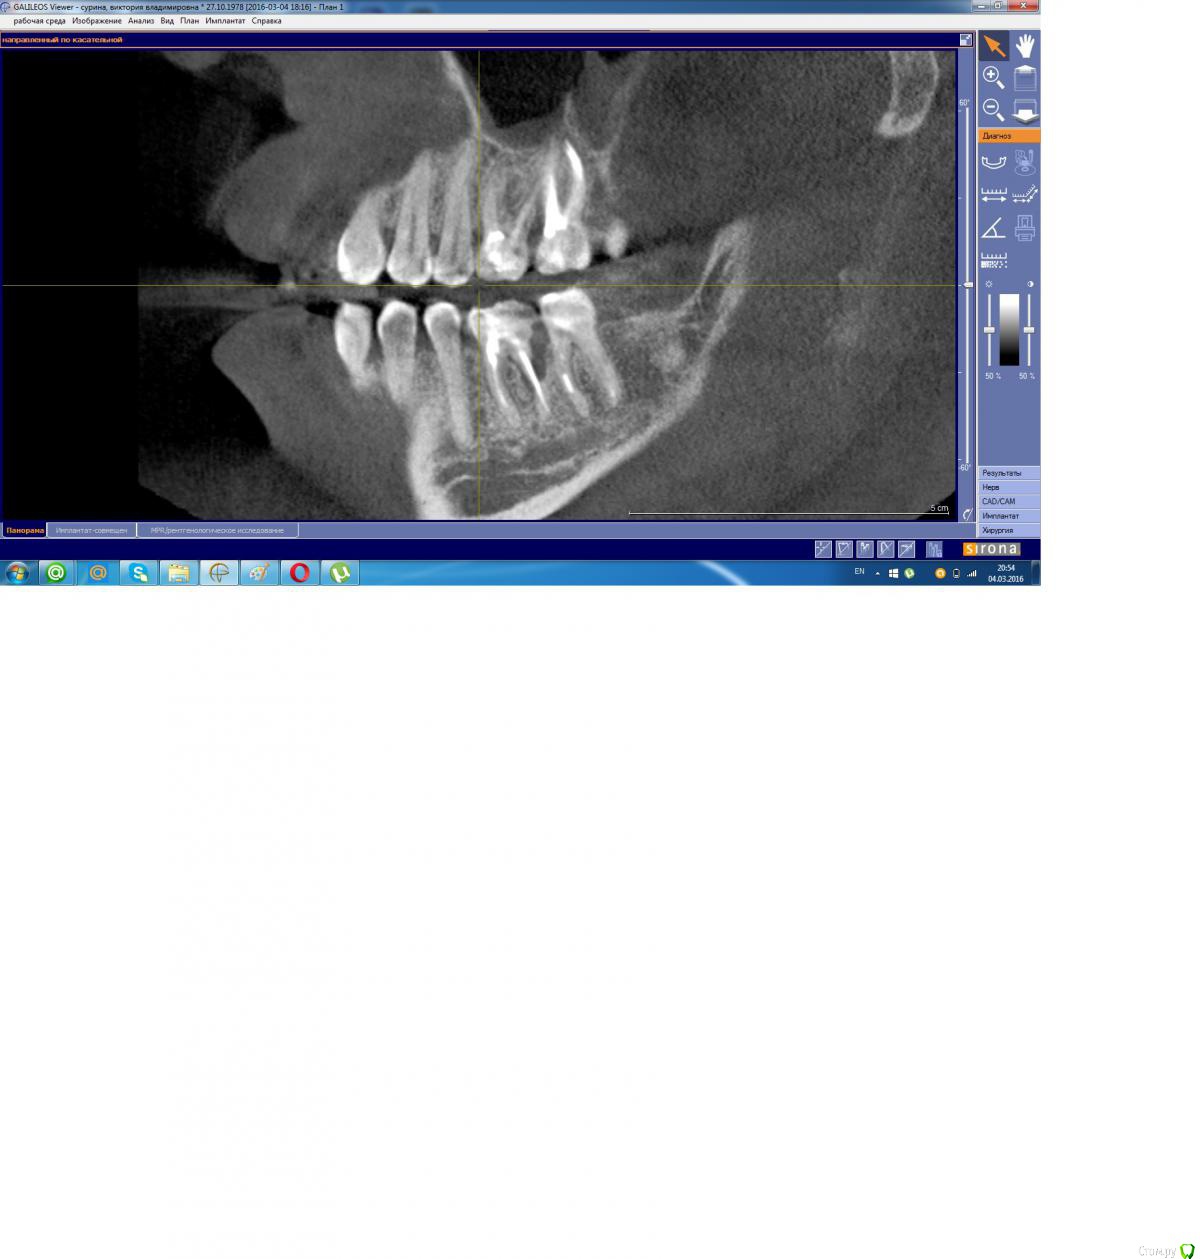

Scorpio Опубликовано 5 марта, 2016 Поделиться Опубликовано 5 марта, 2016 (изменено) Здравствуйте. 3 дня назад под нижней шестеркой образовался абсцесс, боли нет или очень слабая иногда. Вчера обратилась к доктору, сказали удалять зуб. Я отказалась, доктор посоветовала пить антибиотики и полоскать Можно ли сохранить зуб, не удаляя?Снимок прилагаю, если надо, есть КТ.И еще, если возможно по снимку определить, подскажите с какими зубами еще есть проблемы? Изменено 5 марта, 2016 пользователем Scorpio Ссылка на комментарий

Doctor Vlad Опубликовано 5 марта, 2016 Поделиться Опубликовано 5 марта, 2016 док прав. проблемных зубов много... 7ка рядом .. передние зубы внизу... все лечить. 8ки сразу удалять Ссылка на комментарий

Scorpio Опубликовано 7 марта, 2016 Автор Поделиться Опубликовано 7 марта, 2016 Спасибо за ответы. Сегодня иду удалять, хотя отек почти спал, зуб стоит как влитой, вообще не беспокоит, не болит ничего.А верхняя шестерка "распирает" и ее даже слегка можно пошатать пальцами, неужели, это тоже кандидат на удаление в будущем? Обидно, только пролечила все эти зубы в прошлом-позапрошлом году. Но есть один влияющий фактор- грудной ребенок, закончила кормить только в декабре. Ссылка на комментарий

Scorpio Опубликовано 7 марта, 2016 Автор Поделиться Опубликовано 7 марта, 2016 Сейчас почитала про симптомы про 26 , похоже на периодонтит. Зуб лечила год назад. В хорошей клинике, отдала кучу денег. Скажите, могут быть претензии к лечению или это чисто проблемы организма? Ссылка на комментарий

dok1 Опубликовано 7 марта, 2016 Поделиться Опубликовано 7 марта, 2016 Да лечение у вас как раз на достаточно хорошем уровне. Там между зубами карман образовался. Процесс необратимый. Потеря зубов неизбежна. Но чем дольше сохраняете зубы - тем болше кости теряется вокруг них. Ссылка на комментарий

Zlata-doctor Опубликовано 7 марта, 2016 Поделиться Опубликовано 7 марта, 2016 нижний точно на удаление. Все остальное надо смотреть на месте. Я бы не была столь категорична в отношении 25-26. 1 Ссылка на комментарий

red_butler Опубликовано 7 марта, 2016 Поделиться Опубликовано 7 марта, 2016 А верхняя шестерка "распирает" и ее даже слегка можно пошатать пальцами, неужели, это тоже кандидат на удаление в будущем? с верхом на снимке проблем не увидел, лечение выполнено на высоком уровне. Но 2.6 2.7 нужно обязательно протезировать Ссылка на комментарий